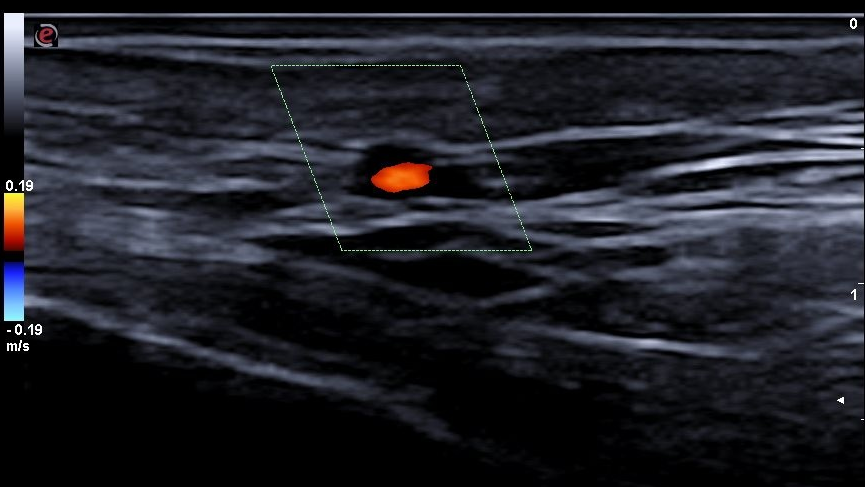

Descripción de los hallazgos ecográficos y las imágenes más relevantes para la resolución del caso

Signo del halo de manera parcheada. Se completa con realización de Doppler de las arterias temporales en ambos lados, observándose en porciones distales en el vaso una hipodensidad sin relleno y disminución del flujo compatible con inflamación del vaso. En tramos proximales se observa buen relleno vascular y flujo sin alteraciones. Todos estos hallazgos con compatibles con alta sospecha de arteritis de la temporal principalmente en sus tramos distales.